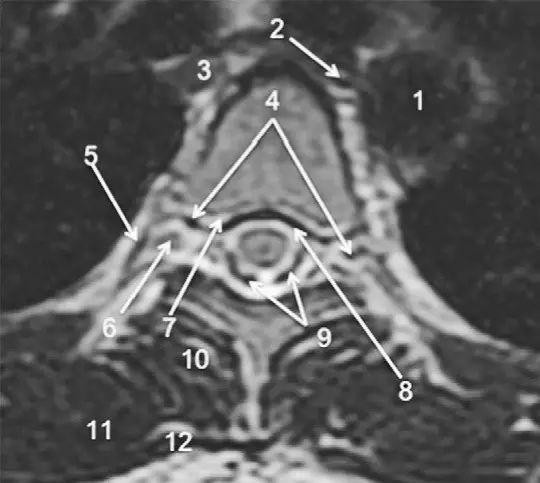

图 2 胸椎 T2WI 轴位图:1,肋椎关节;2,类骨头;3,黄韧带;4,椎弓根;5,椎弓板;6,横突;7,棘突;8,肋横突关节;9,肋结节;10,半奇静脉;11,后纵韧带